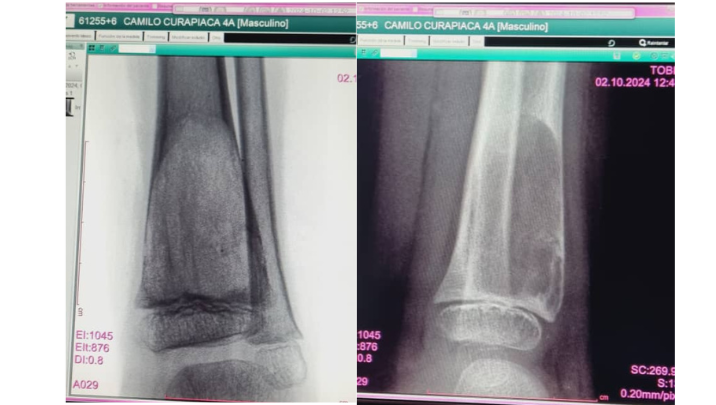

Camilo Andrés, es un niño venezolano de 4 años lleno de energía y sonrisas, pero que en este momento enfrenta un gran desafío. La semana pasada, Camilo fue diagnosticado con un tumor benigno en la tibia izquierda, lo que le ha causado dolor y dificultad para caminar. Su diagnóstico, confirmado por el Dr. Ricardo Sulbarán en el Hospital Ortopédico Infantil de Caracas, indica que necesita una cirugía urgente para remover el tumor y realizar un injerto óseo que permita su recuperación completa.

Camilo debe someterse a una intervención quirúrgica de excéresis del tumor benigno en su tibia izquierda, seguida de un injerto óseo. Esta operación es vital para que pueda crecer y desarrollarse como cualquier niño de su edad, sin dolor y sin limitaciones en sus movimientos.